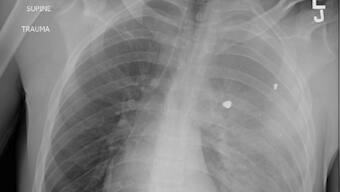

A doctor in US working in an emergency has issued a concerning alert about the primary reason for fatalities among youngsters and adolescents in the United States. Dr. Sam Ghali recently posted an X-ray image on X (previously known as Twitter) depicting the chest of a young boy afflicted by a condition that has now claimed the position of being the chief cause of demise for kids and teenagers in the US. Dr. Ghali posed a question to his followers: “Can you determine the diagnosis?” The image exposes the child’s chest, revealing what seems to be foreign objects lodged within the lungs. “Any guesses? Prayers? To give you a hint, it’s not the FLU, RSV, or COVID,” supplemented Dr. Ghali.

Many of the responses accurately guessed that the image portrayed a gunshot wound. A recent analysis of data from the US Centers for Disease Control (CDC), which was published last week, reiterated that gunshots persist as the predominant cause of death for children in the US during 2021. This research, unveiled in the journal of the American Academy of Pediatrics, brought to light that 4,752 youngsters and adolescents (spanning from newborns to 19-year-olds) lost their lives due to gunshot injuries in 2021. Among these cases, approximately 64% were classified as homicides, nearly 30% as suicides, and 3.5% stemmed from “unintentional injury”. These statistics signify a notable surge of 41.5% in the rate of firearm-related deaths in the pediatric population from 2018 to 2021. “The significant rise in firearm-related deaths among children in 2020 garnered widespread attention, with many speculating that the increase could be attributed to the onset of the 2019 coronavirus disease pandemic and the exacerbation of underlying causes,” elucidated the authors. “Remarkably, even though the initial pandemic-induced fears and anxieties have subsided, firearm-related fatalities continued to hold their position as the foremost cause of death for children and adolescents in 2021.” Up to this point in the current year, data amassed by the Gun Violence Archive indicates that no fewer than 1,187 children and teenagers (ranging from newborns to 17-year-olds) have fallen victim to shootings.